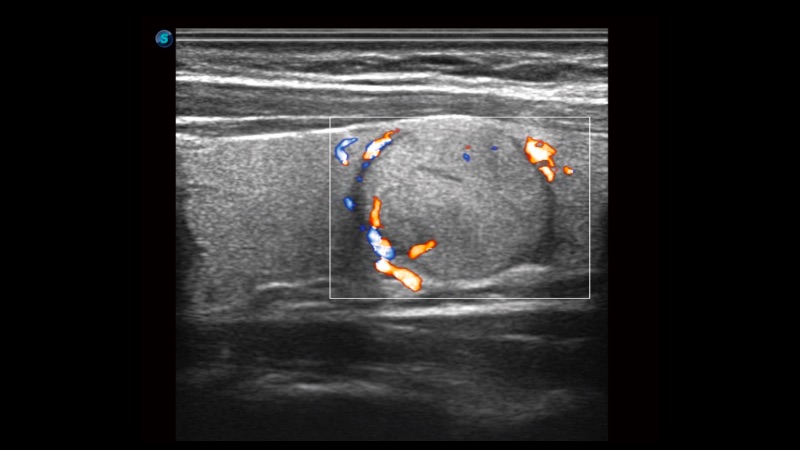

高分辨率血流成像技術(shù)提高了對(duì)低速血流信號(hào)的檢測(cè)能力。在提高空間分辨率的同時(shí),也克服了血流外溢現(xiàn)象,為用戶提供更加真實(shí)的血流動(dòng)力學(xué)信息。